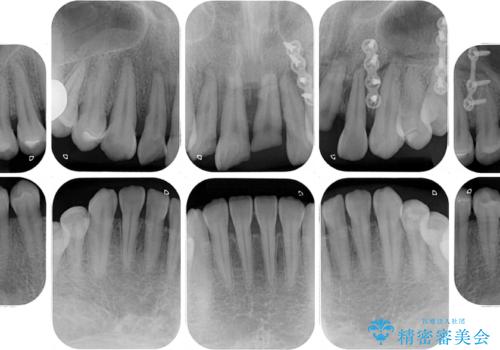

- ソーシャルメディアでのゲームに夢中になっている最中に車と接触し、前歯の抜歯を余儀なくされた患者様です。

初診時では前歯が保存できる可能性も模索しましたが、損傷が激しく3歯を抜去することとなりました。

保存となった隣在歯も神経が失活していており、補綴治療が必要であったので、オールセラミッククラウンにて補綴治療することとしました。

奥歯には元々欠損があり、欠損に伴う咬合不正も認められたため、部分矯正を行った上でインプラント補綴治療も行うこととしました。